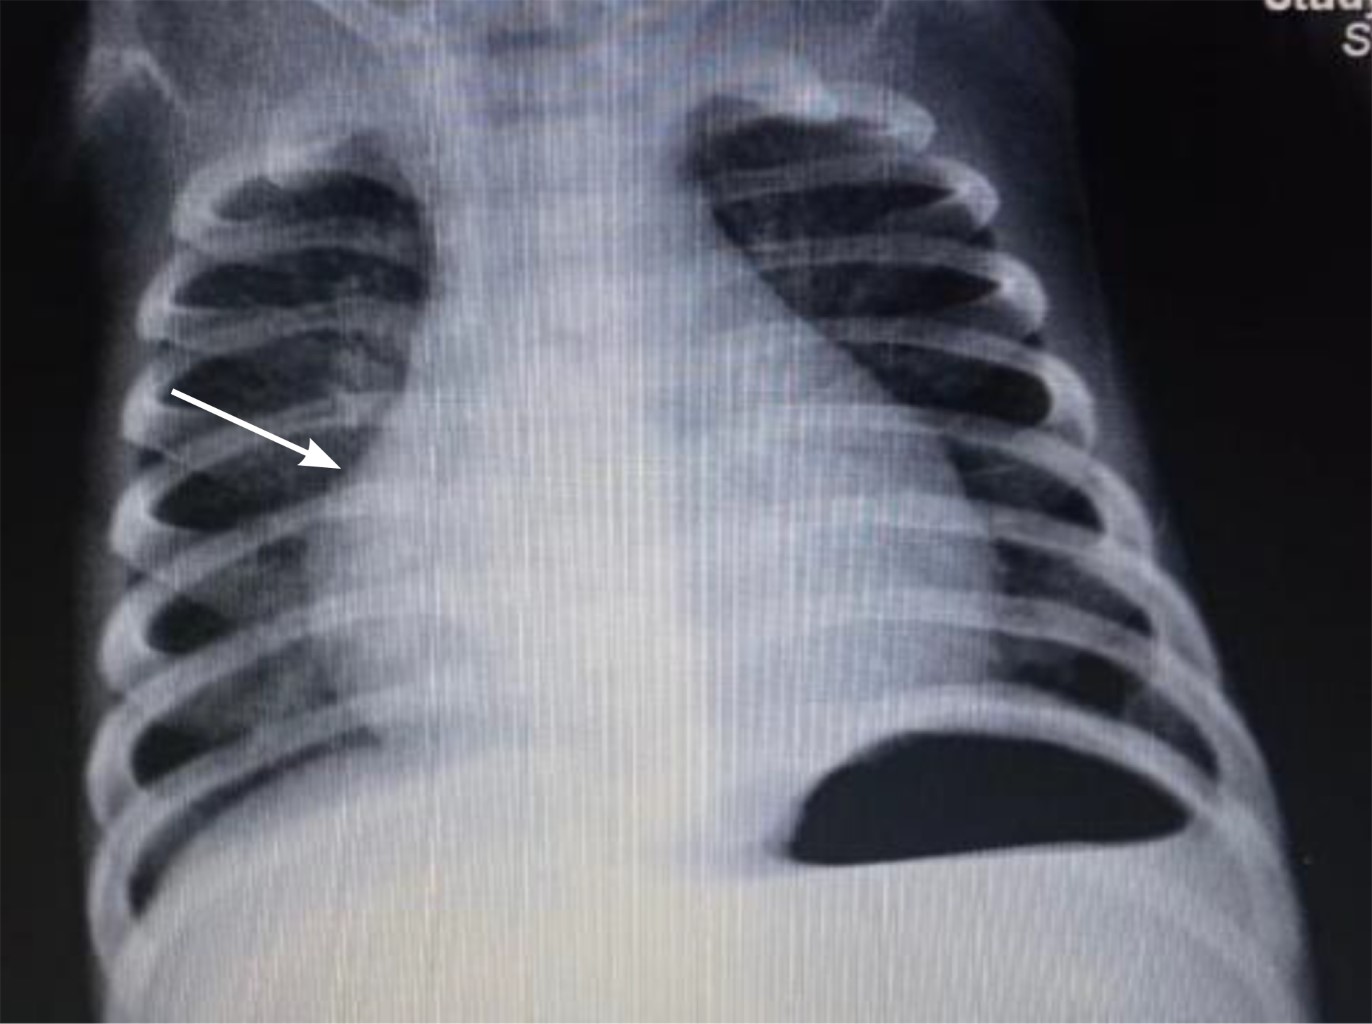

Intracardiac hemangioma in an infant

Peña-Guevara H, Vázquez-Pérez A, Figueroa-Vega JR, Quibrera-Matienzo JA

Introduction: intracardiac tumors in children are rare, but most are benign. In general, these tumors do not cause symptoms, but as they increase in size, they can lead to heart failure. Case presentation: three-month-old male patient who had an intrauterine diagnosis of mediastinal mass. At birth he was asymptomatic. Resection of right atrial tumor was performed. The pathology report indicated that it was an intracardiac hemangioma. The patient has had a favorable evolution. Conclusions: intracardiac tumors are a rare entity in pediatrics, which are generally detected accidentally.

Figure 1

Figure 2

Figure 3

Figure 4

Figure 5

Figure 6

Figure 7

Figure 8